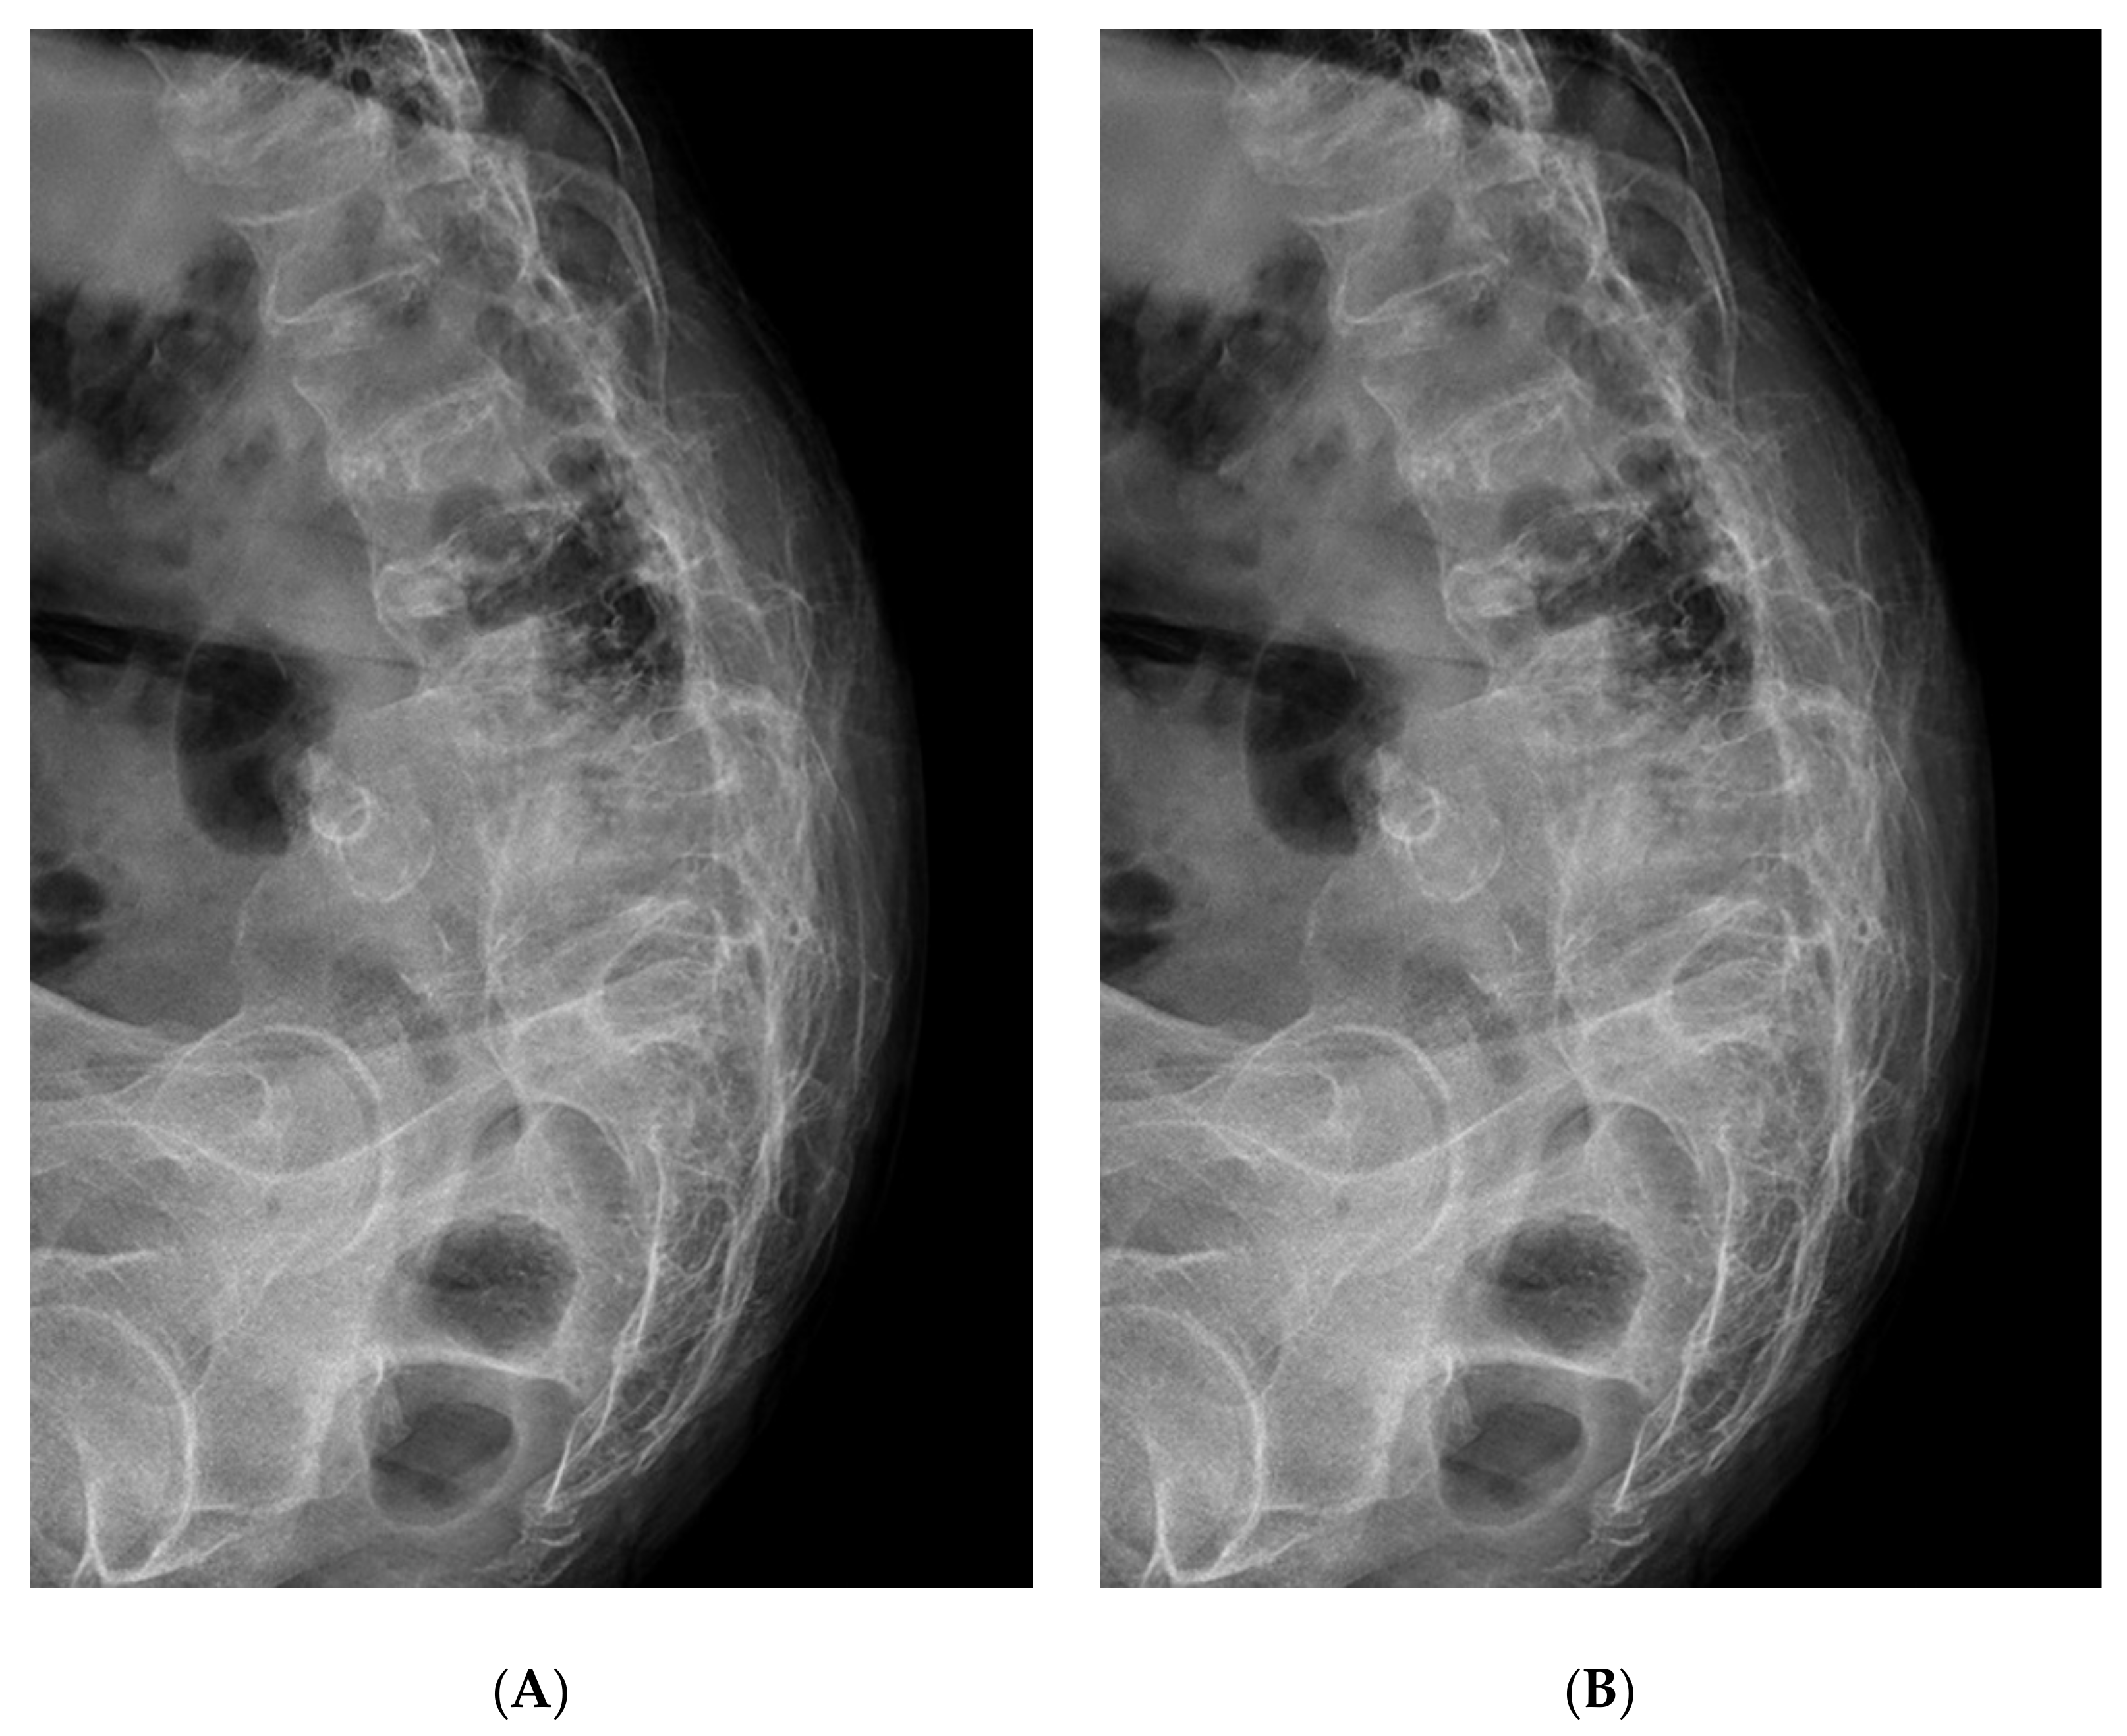

2. Case Presentation